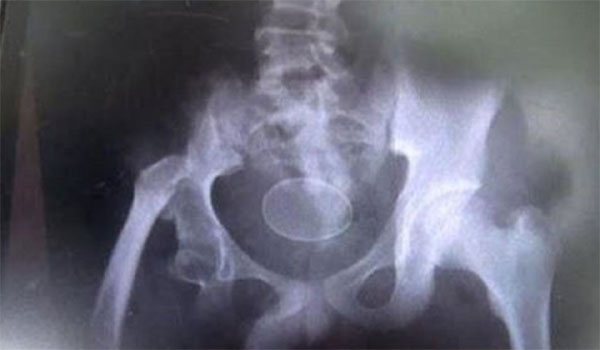

Ο 14χρονος πρωταγωνιστής της ιστορίας είναι ο Ακμάλ Ρουσλί, ο οποίος μεταφέρθηκε την Τρίτη στο νοσοκομείο με έντονους πόνους στην κοιλιά. Όταν οι γιατροί του έκαναν τον απαραίτητο υπέρηχο, διαπίστωσαν πως μέσα στην κοιλιά του 14χρονου αγοριού, υπήρχαν δύο… αυγά κότας.

Τον ρώτησαν αν τα κατάπιε και το αρνήθηκε. Οι γιατροί τον πίστεψαν, καθώς τα αυγά ήταν ολόκληρα στην κοιλιά του. Τελικά, οι γιατροί αφαίρεσαν με επέμβαση τα δύο αυγά από την κοιλιά του 14χρονου, ωστόσο, ο πατέρας του τους ενημέρωσε πως όταν το παιδί ήταν 12 ετών είχε μεταφερθεί με έντονους πόνους και πρήξιμο στο νοσοκομείο και οι γιατροί διαπίστωσαν ότι υπήρχαν 18 αυγά μέσα στην κοιλιά του, αλλά και στο έντερο. Σε εκείνη την περίπτωση, τα αυγά αφαιρέθηκαν από το παιδί μέσω του πρωκτού και του χορηγήθηκε ειδική αγωγή.